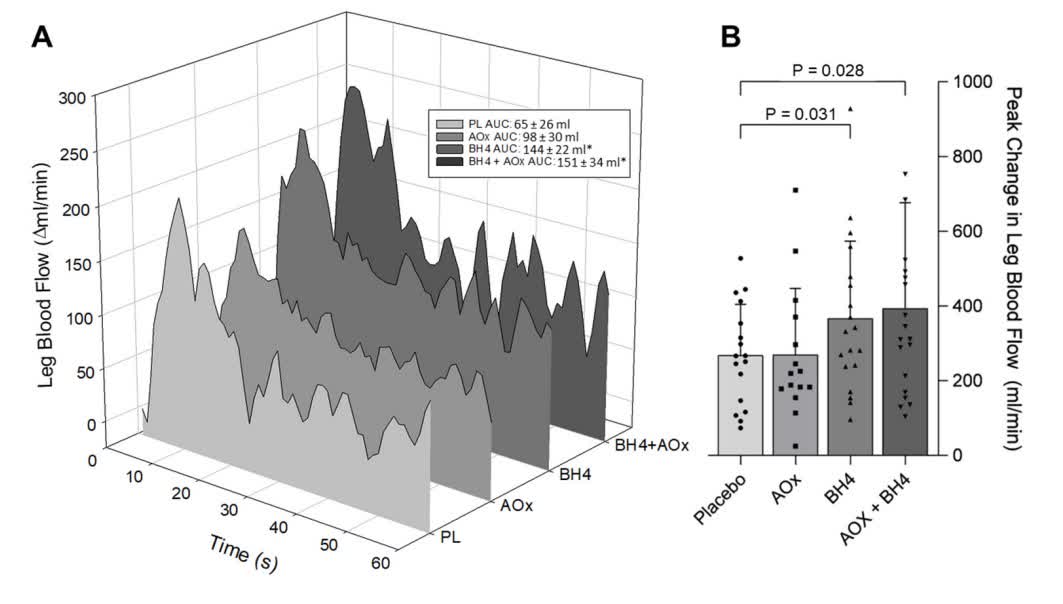

New evidence for the efficacy of acute BH4 administration to improve peripheral microvascular function in patients with heart failure @JJRyanMD Kanokwan (Mandy) Bunsawat, PhD @jaysongifford D. Walter Wray #AHAJournals ahajrnls.org/3YV1Q9F